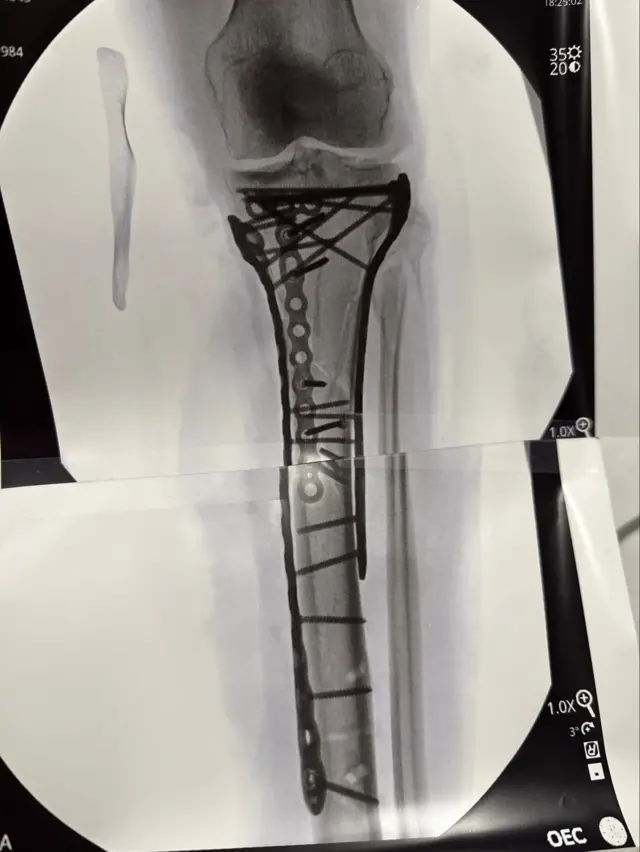

Скијашка звезда је имала шест операција откако је сломила ногу и скочни зглоб у женском спусту у Италији 8. фебруара.

Имала сам синдром компартмента, притисак унутар мишиц́а, који ограничава проток крви, а хирург ме је хитно оперисао како би ублажио притисак, додала је.

„Отворио је обе стране моје ноге, тако да је била отворена и пустио је да дише, такорец́и. Спасио ме је“, рекла је 41-годишња скијашица.

По повратку у САД, Вон је рекла да је имала нову операцију која је трајала шест сати.

Вон је рекла да би могло да буде потребно годину дана да јој кости зарасту.

„Онда ц́у одлучити да ли желим да извадим све метале из ноге или не, а онда ц́у поново на операцију због предњих укрштених лигамената (раније повреде, пре ЗОИ).“